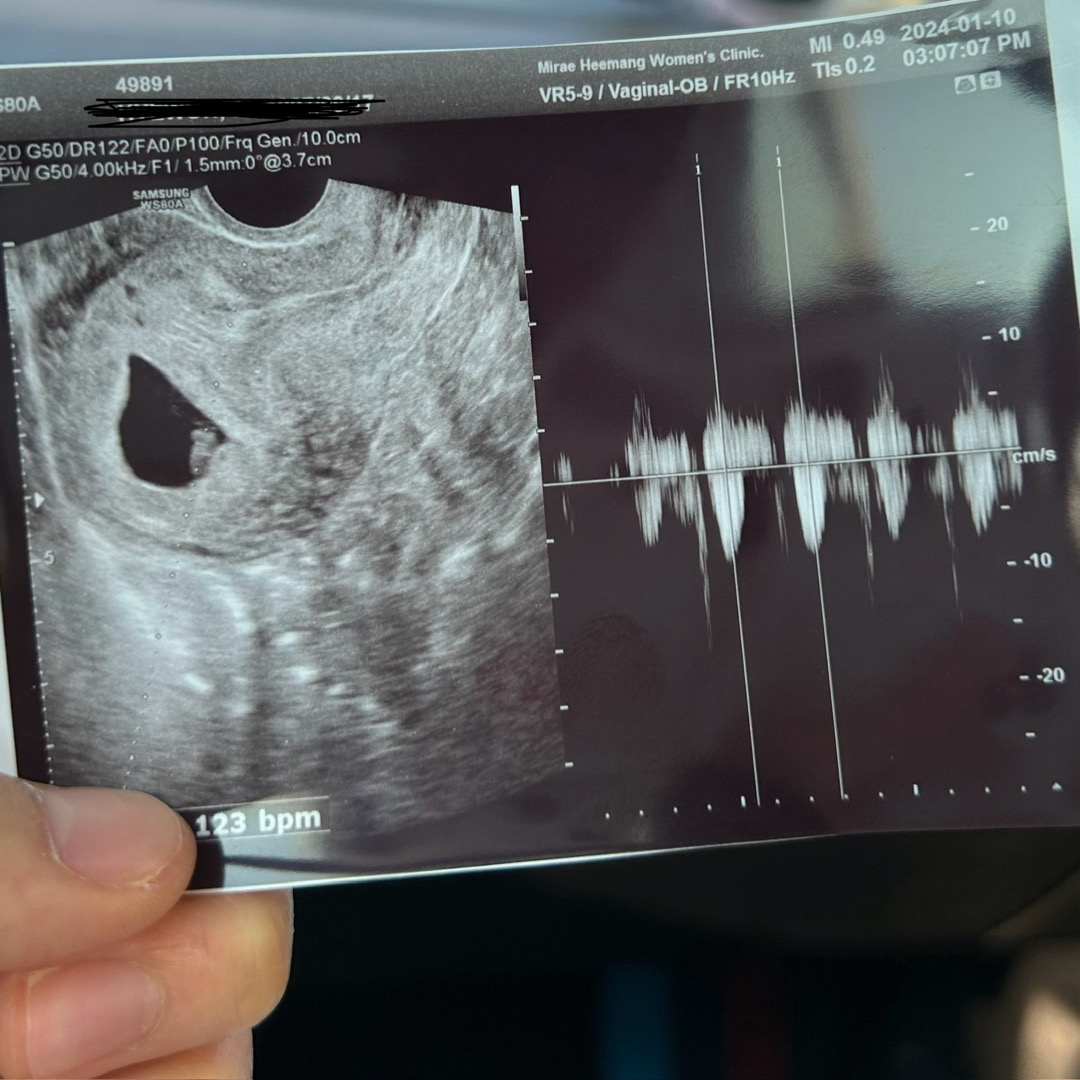

첫 심장소리 들었어요!!

원래는 다음주에 내원이였는데 입덧이 너무 심하여 약처방받으러 간김에 아가 잘있나 싶어서 초음파까지 보고왔는데 ㅎㅎ 선물처럼 심장소리까지 듣고왔네요! 막생 11월28일이구 6주 1일인줄 알았는데 조금 당겨져서 6주5일정도 된거같다 하셔서 8월 베동으로 넘어왔네용 ㅎㅎ 예정일은 8월 31일 입니다!♥️ 아기집 3.7cm 아기는 1.5mm래욤 ㅠㅠ초귀요미.. 심장도 123bpm으로 우렁차다고 합니다 남편이랑 갔더니 남편 눈물 찔끔 ㅎㅎ마음이 살짝 놓이네요! 다들 화이팅 합시닷😊

1.5mm인데 6주5주 잡혔나요? 저흰 6주5주인 줄알고 갔는데 아가 2.6mm(133bpm)여서 6주1일로 줄었 거든요~ 선생님이나 기계에 따라 주수가 다르기도 한가보네요